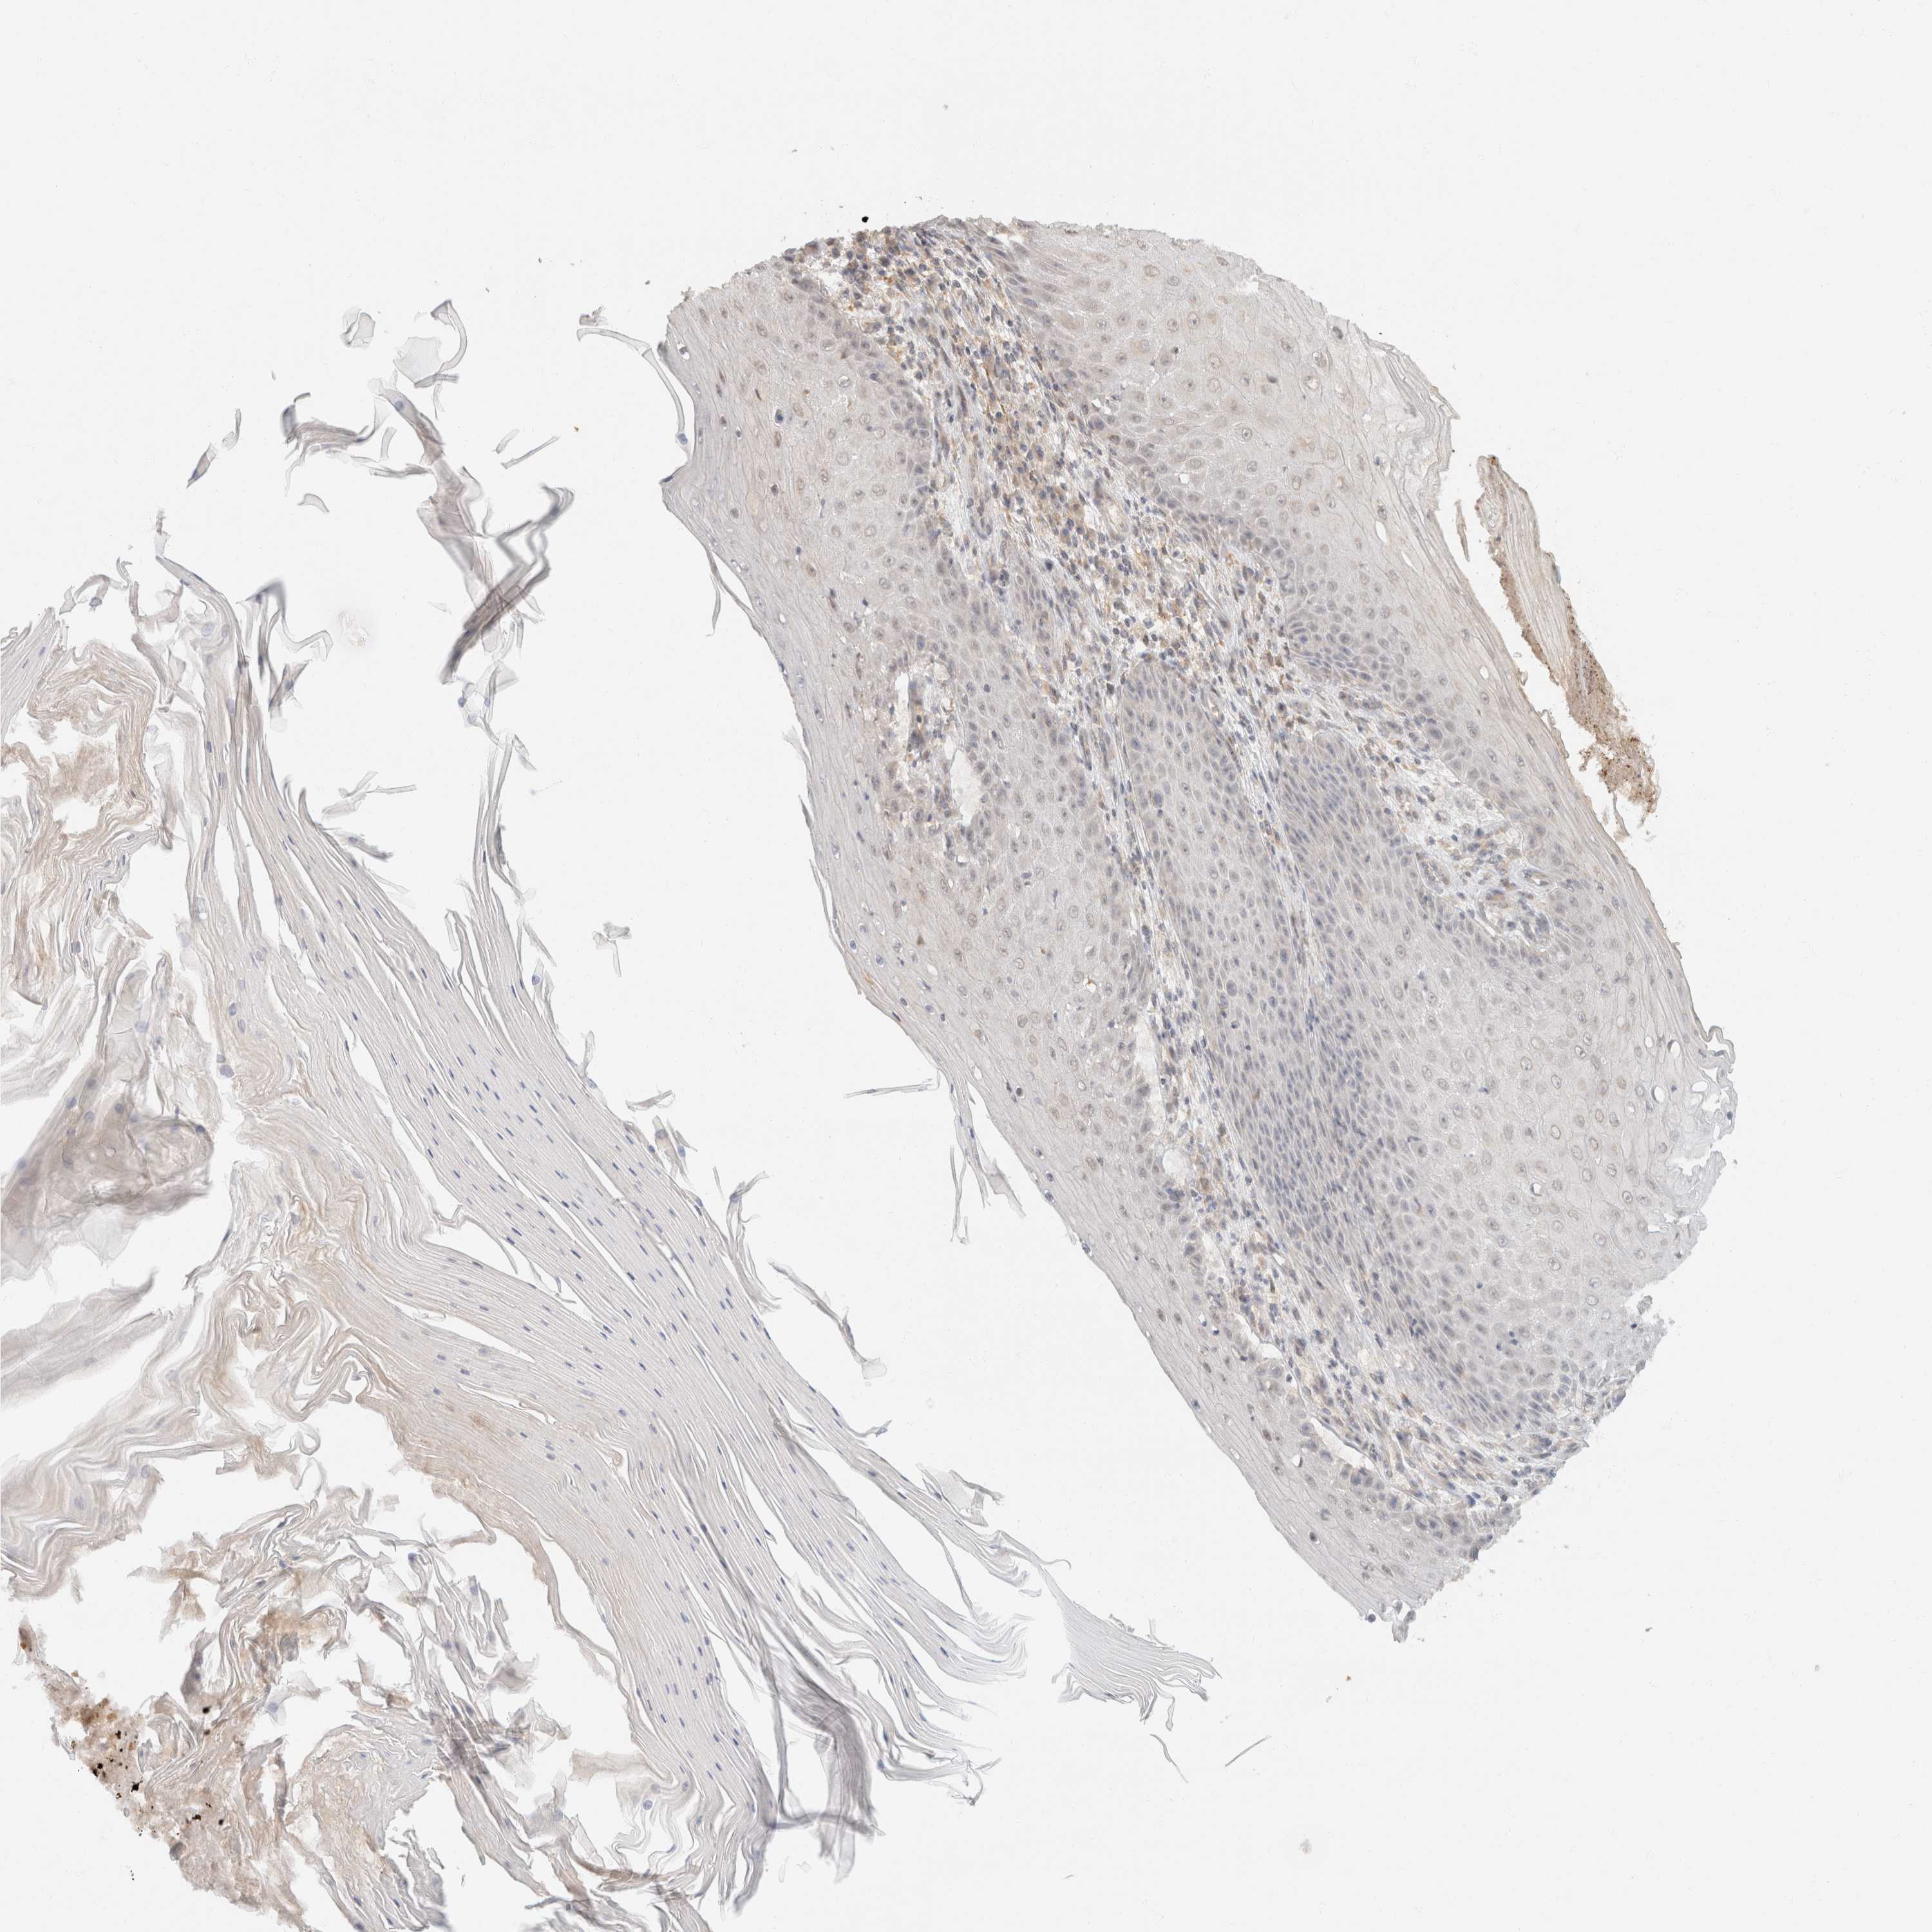

SKIN CANCER - Protein expressioni

A mouse-over function shows sample information and annotation data. Click on an image to view it in a full screen mode. Samples can be filtered based on level of antibody staining by selecting one or several of the following categories: high, medium, low and not detected. The assay and annotation is described here.

Each image is clickable and will lead to virtual microscopy that enables deeper exploration of all samples and also displays staining intensity scores, fraction scores and subcellular localization as well as patient and tissue information for each sample.

Antibody HPA024702

Antibody CAB017041

Staining

High

Medium

Low

Not detected

Intensity

Strong

Moderate

Weak

Negative

Quantity

>75%

75%-25%

<25%

None

Location

Nuclear

Cytoplasmic/membranous

Cytoplasmic/membranous,nuclear

Basal cell carcinoma

Squamous cell carcinoma, NOS

Squamous cell carcinoma, metastatic, NOS